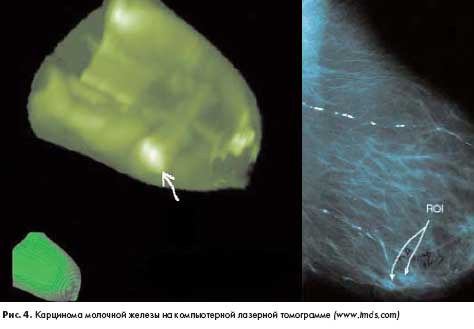

Принципиально иной метод исследования молочной железы предложен компанией "Imaging Diagnostic Systems" (США). Компьютерная лазерная томография имеет некоторое сходство с традиционной томографией, но рентгеновская трубка заменена источником лазерного излучения, а специальный алгоритм обработки полученных "срезов" позволяет получить трехмерные высокоинформативные изображения. Молочная железа помещается в сканирующую камеру, а облучение лазером производится по окружности, причем каждый новый виток сканера смещается на несколько миллиметров от основания груди к ее периферии. Полученные изображения позволяют выявить и интерпретировать неореваскуляризацию и другие отклонения от нормы (рис. 4).